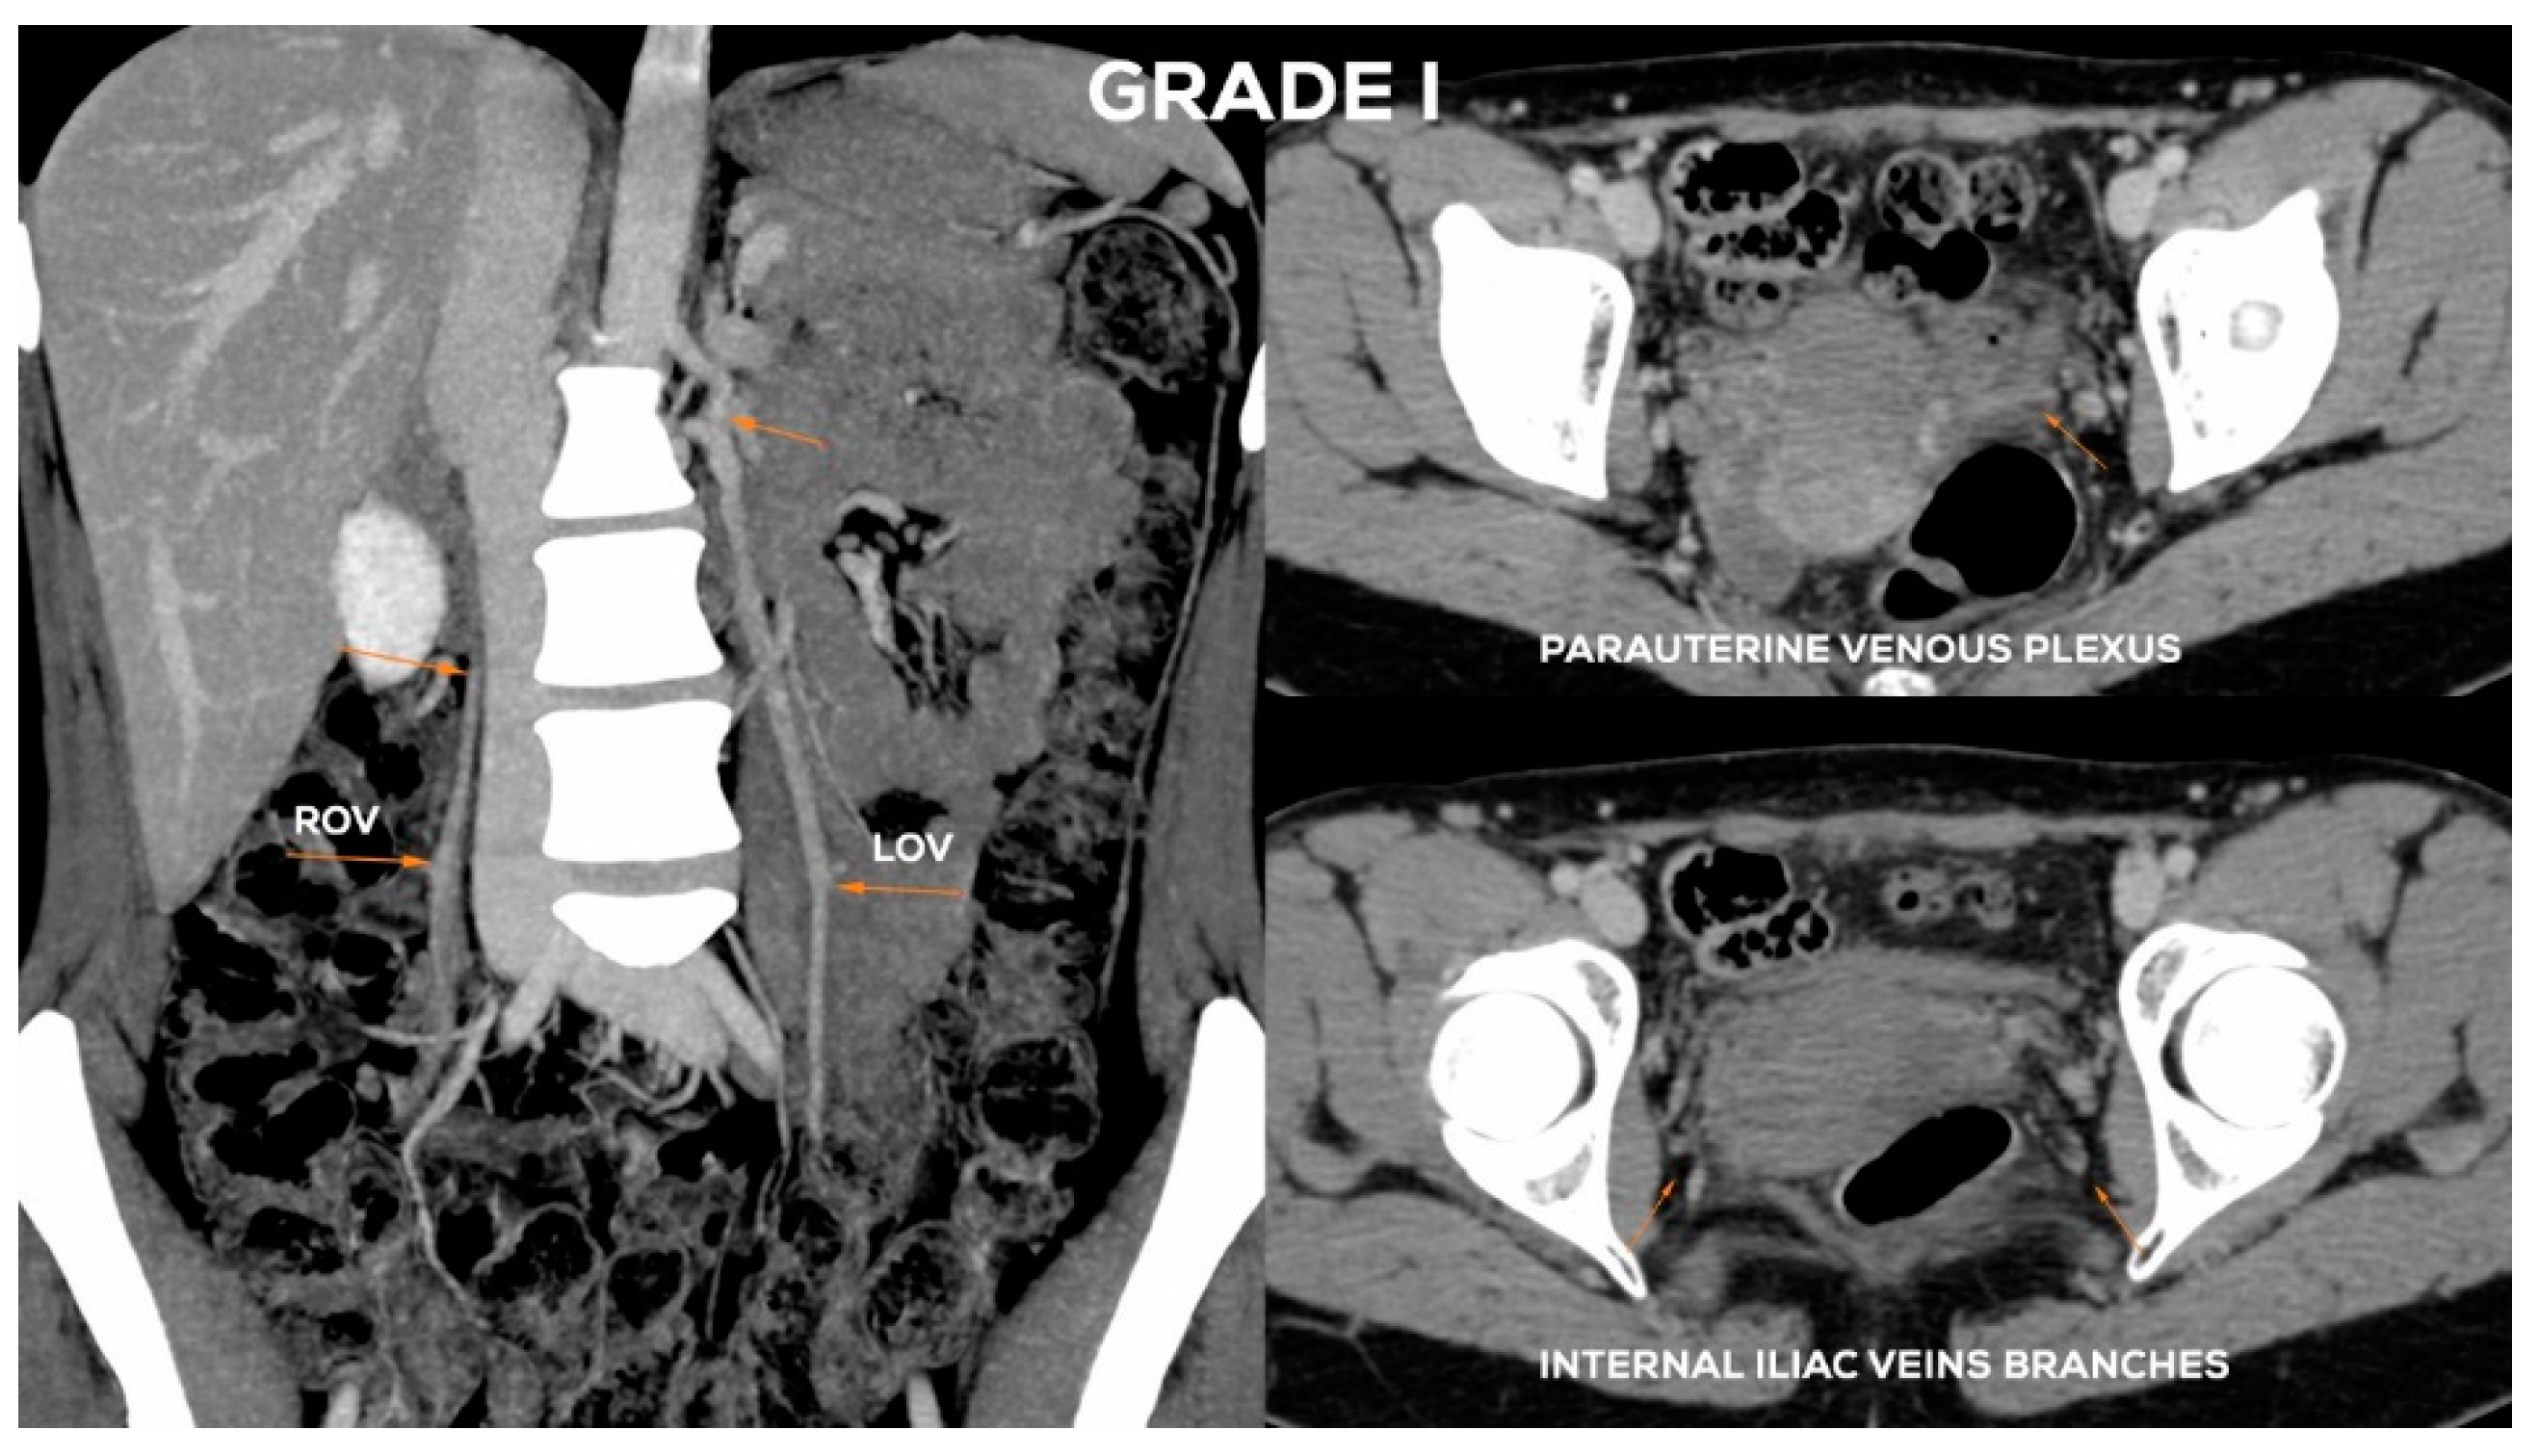

Figure 9.

Typical findings in patient with Grade I ovarian veins insufficiency seen on a CTV images in coronal and axial planes.

Figure 10.

Typical findings in patient with Grade I/II ovarian veins insufficiency seen on a CTV images in coronal and axial planes.